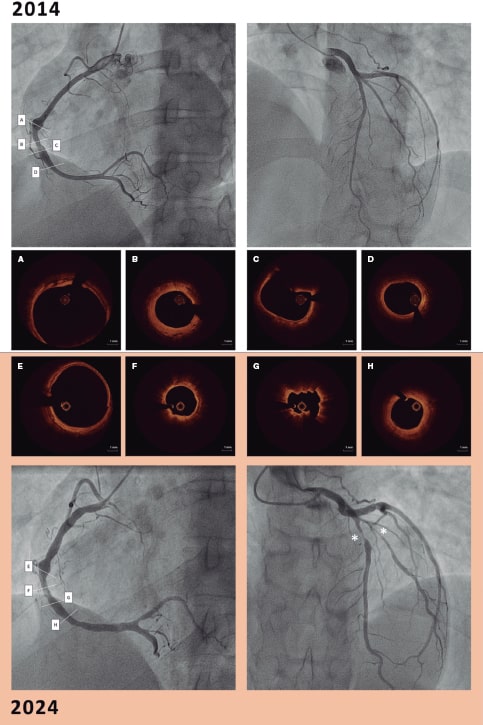

En 2024, se realizó una nueva coronariografía debido a una angina de esfuerzo que confirmó el avance de la enfermedad en la CD y una mayor calcificación en la parte media de la misma, según evidenció la OCT realizada en el mismo segmento arterial. Además, el segmento distal confirmó el avance de la enfermedad con engrosamiento intimal y rotura de la túnica media (figura 1; figuras 1E-H). El hallazgo de una nueva estenosis crítica en la descendente anterior propició que se biopsiara un segmento aneurismático de la arteria temporal (figura 2). Los hallazgos histopatológicos fueron similares a los observados en el OCT de las coronarias. La pared arterial engrosada evidenció la presencia de hiperplasia intimal fibrótica/miofibroblástica, infiltrado inflamatorio agudo, necrosis y cambios fibrinoides (figura 2A, flecha) y una pérdida de la lámina elástica interna (figura 2B, flecha; figura 2A, asterisco) y vasos adventicios, lo cual confirmó la presencia de inflamación crónica perivascular.

Figura 2.

Teniendo en cuenta los síntomas y hallazgos en la descendente anterior (engrosamiento intimal y rotura de la túnica media, sugestivos de vasculitis; figura 3A, asterisco y flecha) y la presencia de un vaso distal sano (figura 3A, doble asterisco), se optó por realizar una intervención coronaria trastorácica con balón farmacoactivo (figura 3B).

Figura 3.